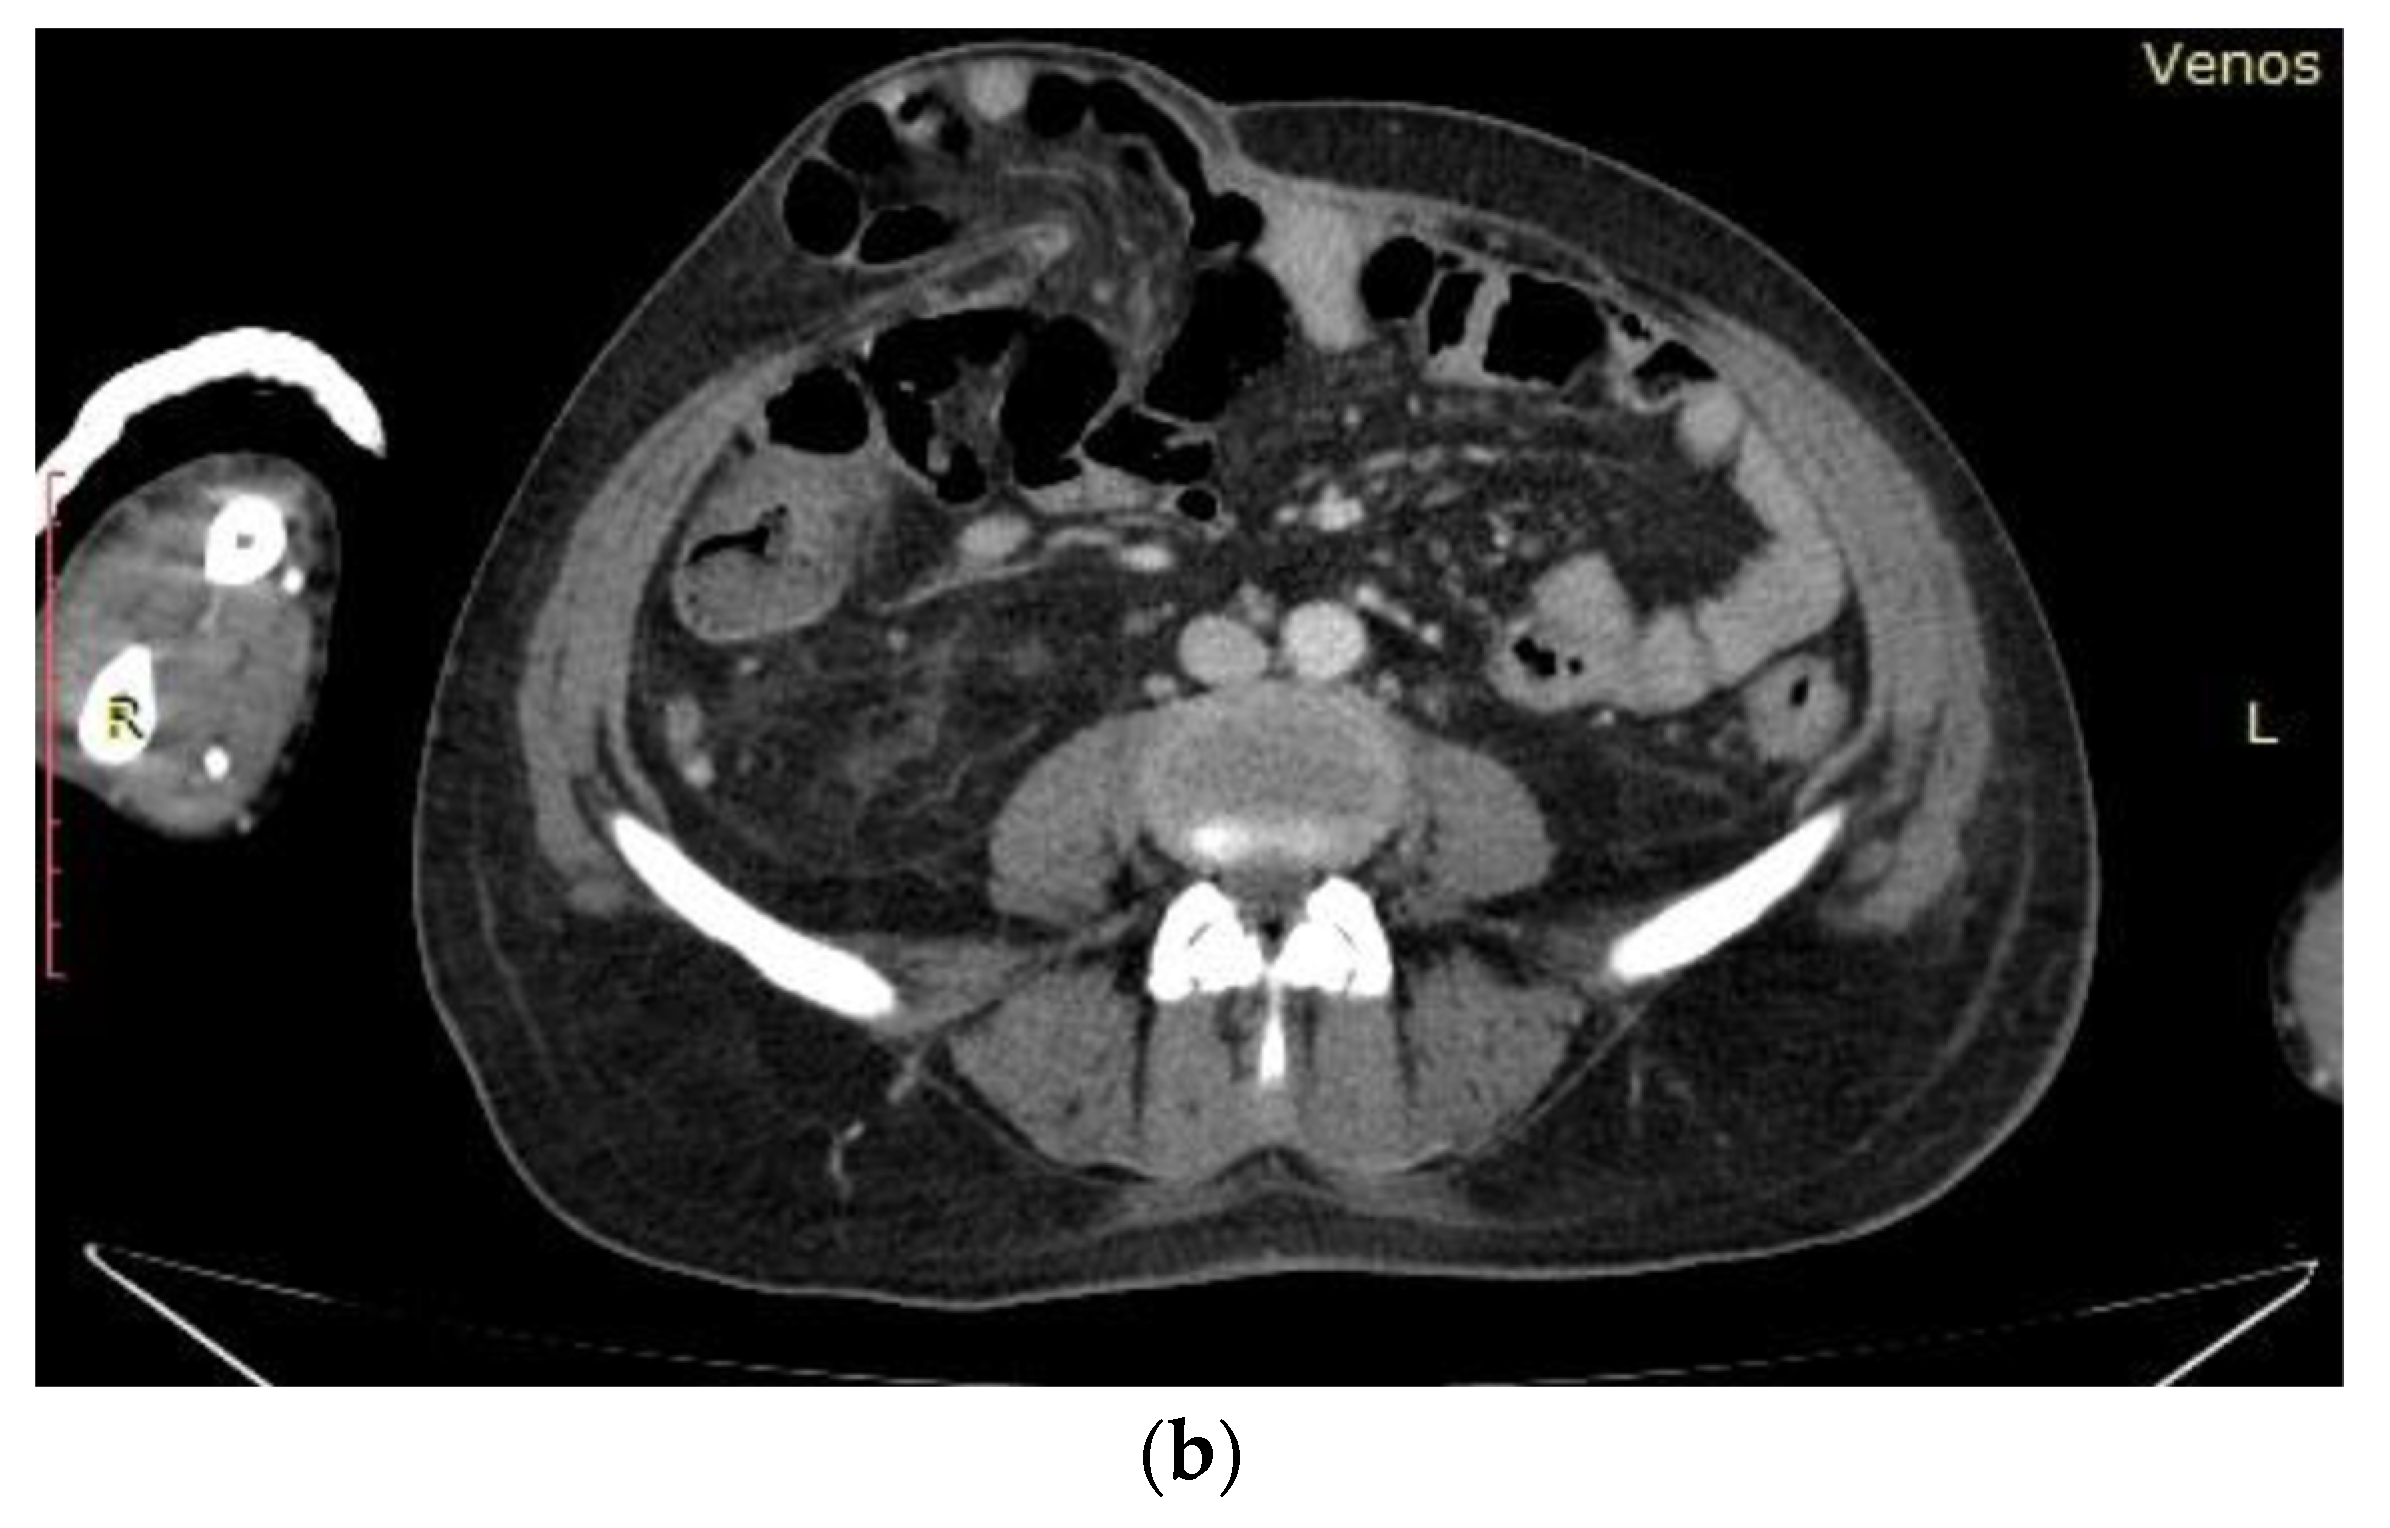

Further, Computed Tomography Angiography (Angio CT) highlights the extravasation of the contrast substance at the level of the colon (Figure 4b), and urgent surgical intervention is required, performing a right hemicolectomy. Other findings on the Angio-CT examination were dysmorphic liver, permeable portal system (portal vein diameter—15 mm); appearance of chronically damaged kidneys, small in size with left renal lithiasis; the absence of contrast of the left renal artery; liquid in hypogastrium with maximum thickness of 19 mm; multiple lumbar-aortic adenopathies on the mesenteric artery root, ileo-colic and bilateral inguinal with maximum dimensions of 15/10 mm; calcified atheromatosis of the aorta and its emergent arteries; right pleural fluid of 12 mm, “frosted glass” areas of the level of the lower right lung lobe; and a pericardial fluid layer.

(a) Anterior chest X-ray showed the accentuation of the bilateral lung pattern and horizontal heart; (b) Angio CT highlights the extravasation of the contrast substance at the colonic level.